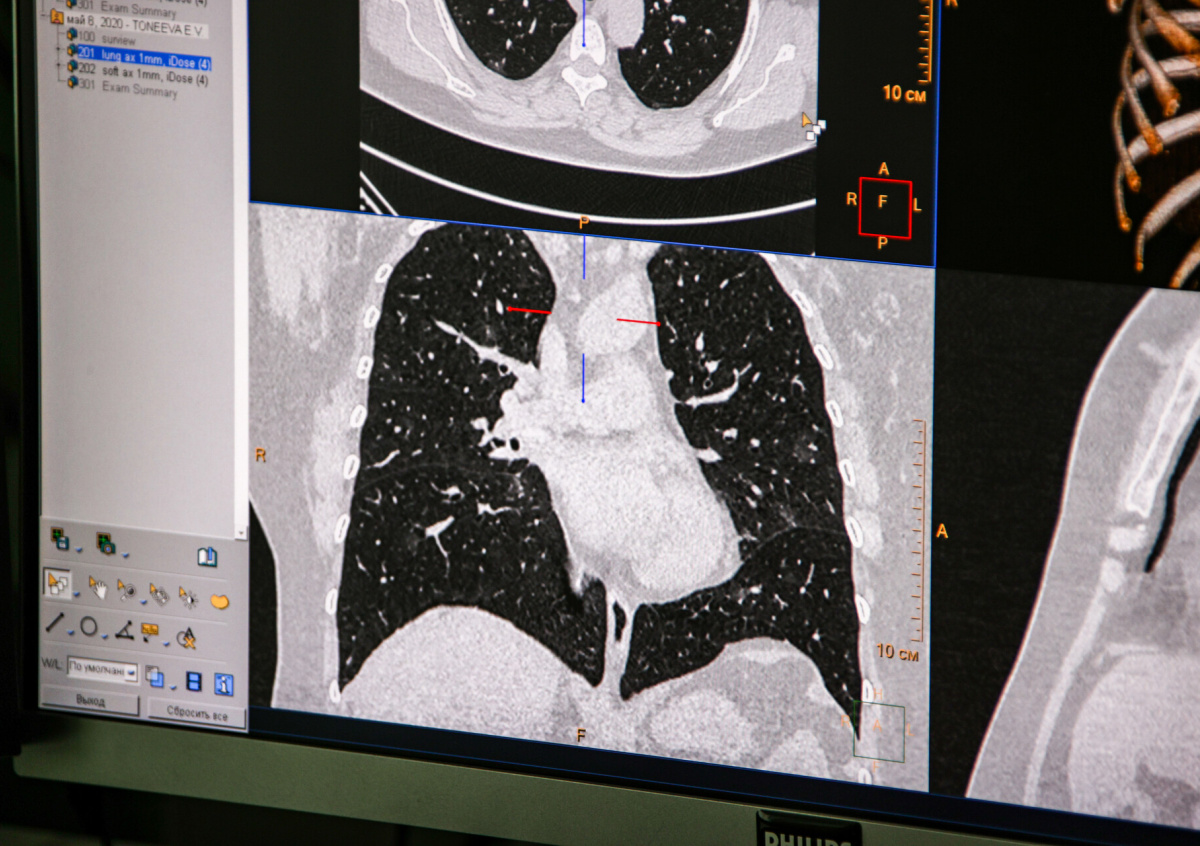

Фото: Сергей Лантюхов/NEWS.ru

Почти 10 тысяч россиян полностью вылечились от коронавирусной инфекции за сутки. Как сообщили 20 октября представители федерального оперативного штаба по контролю и мониторингу ситуации с распространением COVID-19, число выздоровевших составило 9704 человека.